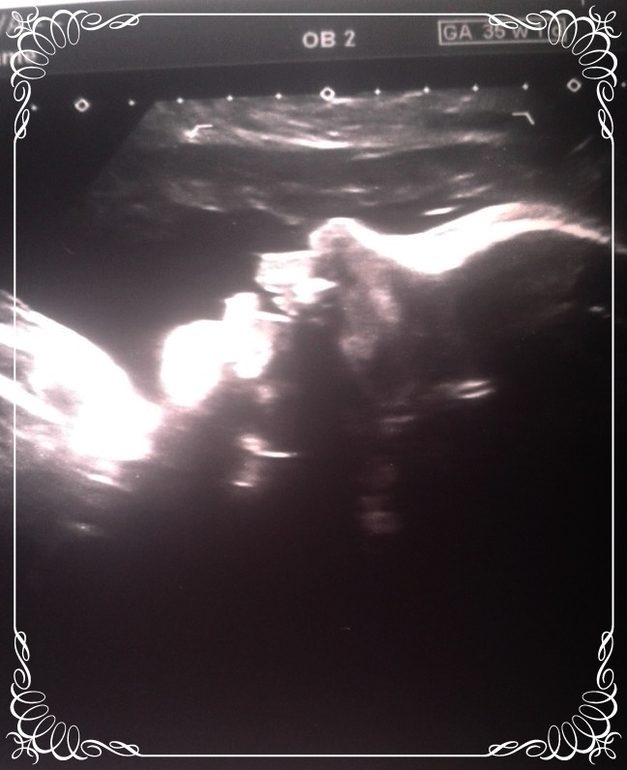

Мое последнее узи в эту беременность ♥

УЗИ, КТГ, доплерСегодня нам 35+1 и последняя встреча с малышом в животике.

♥ Да да у нас все еще сыночек в животе - ничего не усохло и не отвалилось

Показали кокошки и писюлек. Даже фоточку сделали.

♥ Сердечко бьется 139 ударов в минуту (да и сынулька вел себя спокойно)

♥ Весим уже 2900 г (напомню, что в 30 недель вес был 1480), врач добавила, что к пдр вес малыша будет не больше 3500. Так что очень надеюсь, что в этот раз не порвусь

♥ Окружность головы 323 мм, окружность живота 324 мм, длина плеча/бедренной кости 61/67 мм, БПР 93 мм

♥ Плацента по передней стенке толщиной 40 мм и 2 степени зрелости, нижний край выше зева на 8 см

♥ Пуповина из трех сосудов и обвитий нет

♥ Пороков и аномалий не обнаружено

♥ По допплеру все отлично

♥ И малыш развит на 36 недель

Фоточка на память (сынок видимо поет или что-то узисту рассказывает

):